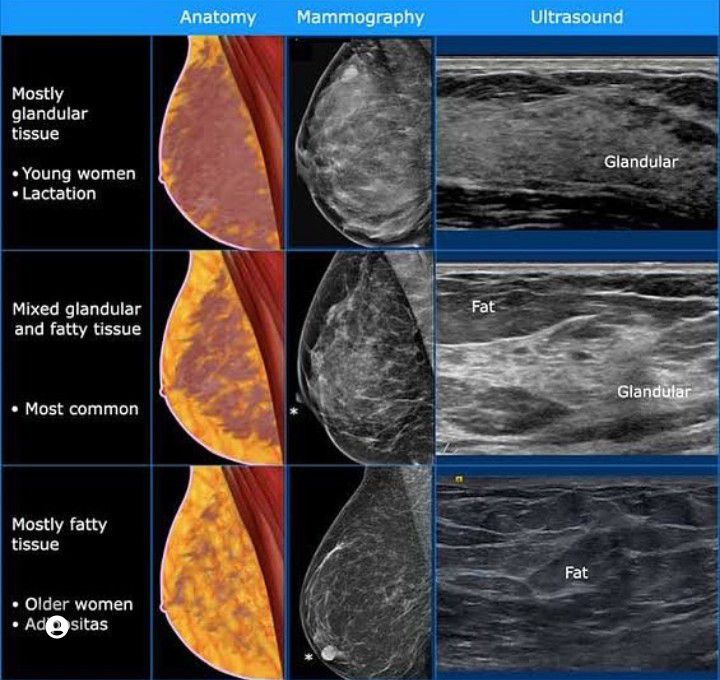

Breast Tissue

Here you can appreciate different views of breast tissue on different types of imaging.